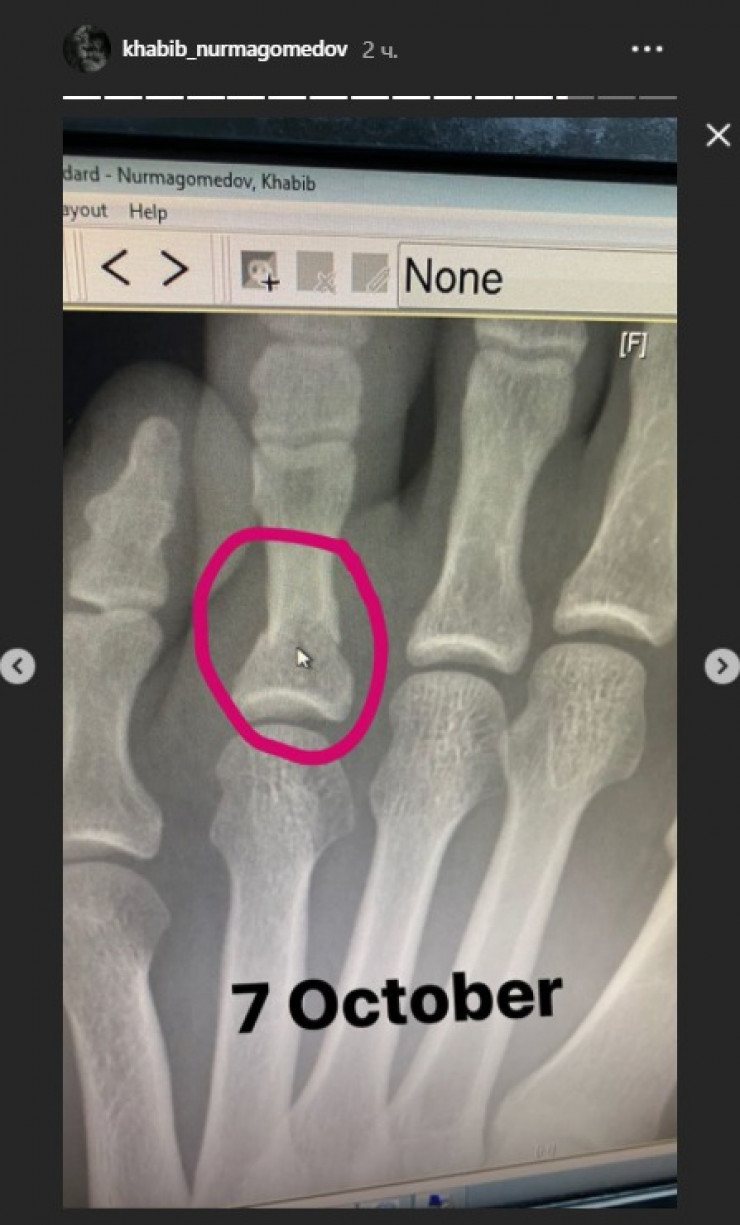

Россиянин также опубликовал рентгеновский снимок пальца ноги.

Ранее сообщалось, что за три недели до боя с американцем Джастином Гэтжи Хабиб Нурмагомедов обращался в больницу по поводу перелома.